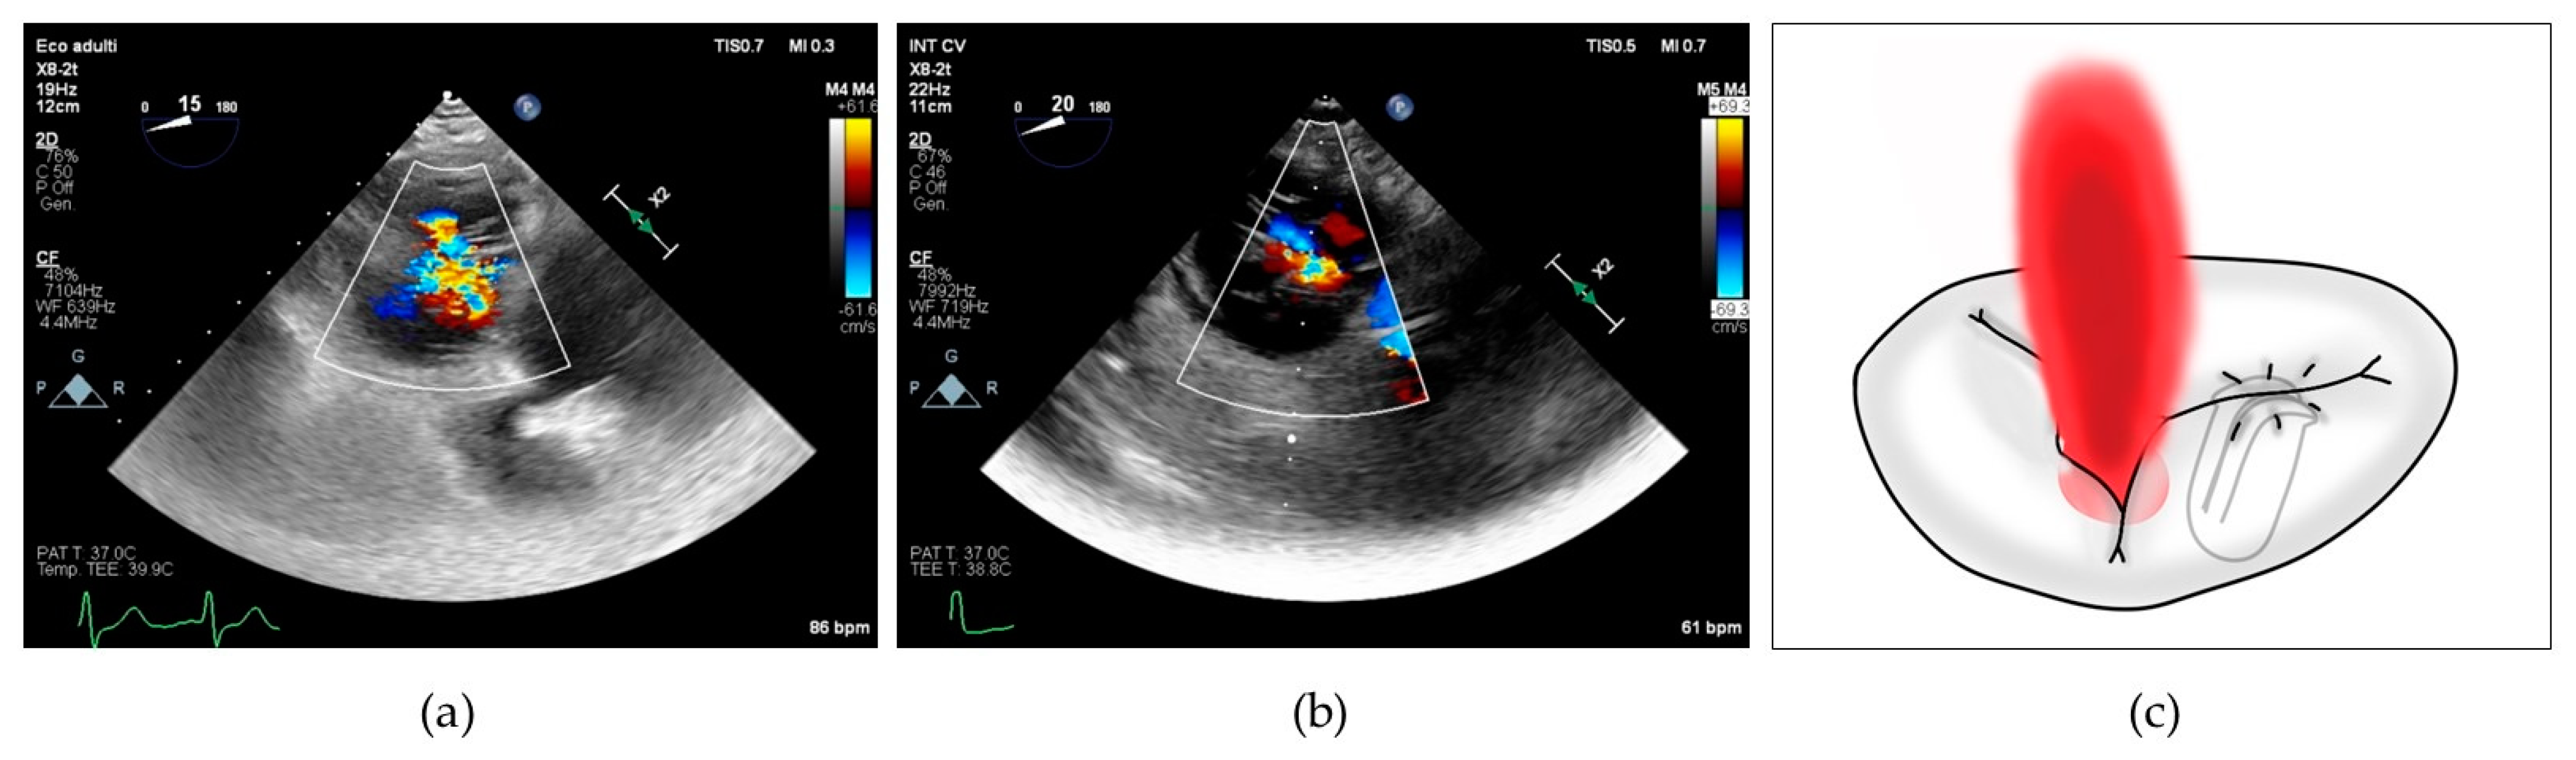

The SL-LAI was calculated by the sum of the lengths of septal and anterior leaflets normalized for the SL annulus diameter as previously described [16]. However, in our center experience, many patients treated with initial antero-septal grasping showed an intraprocedural persistence of significant TR and needed a second device implantation, often grasping the posterior leaflet. Therefore, we developed a novel modified leaflet-to-annulus index (LAI) derived from the sum of the anterior and posterior leaflets, normalized for the antero-posterior annulus diameter and we defined it as the AP-LAI (see Figure 1).

Figure 1. (a) Drawing showing tricuspid valve annulus and leaflets and the measures of antero-posterior diameter (red dotted line) and septal–lateral diameter (blue dotted line); (b) 3D transesophageal echocardiography with MPR reconstruction showing antero-posterior diameter measure (red) and anterior (green) and posterior (blue) leaflet measurement for computing the antero-posterior leaflet-to-annulus index; (c) 2D transesophageal echocardiography with orthogonal cross-section view showing the measure of septal–lateral diameter (red), septal (green) and anterior (blue) leaflet diameter for computing septal–lateral leaflet-to-annulus index; Abbreviations: Ant—anterior, AP—antero-posterior, Pos—posterior, Sep—septal, LA—left atrium, RA—right atrium, RV—right ventricle, SL—septal–lateral.